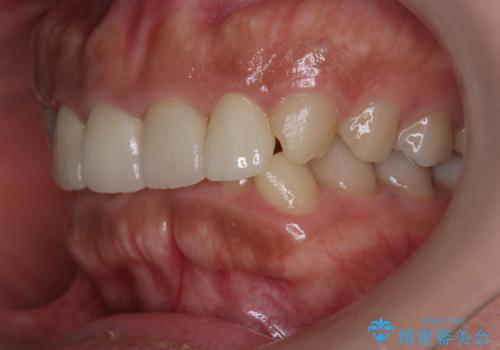

欠けた前歯を綺麗にしたい

- 「欠けてしまった前歯のコンポジットレジン修復をくり返していたが、すぐ外れてしまい困っている。」

、と前歯の欠けの改善を求めて来院されました。

噛み合わせが深く、前歯の突き上げが大きいため欠けの繰り返しを防ぐべくセラミッククラウンによる補綴を行うこととしました。